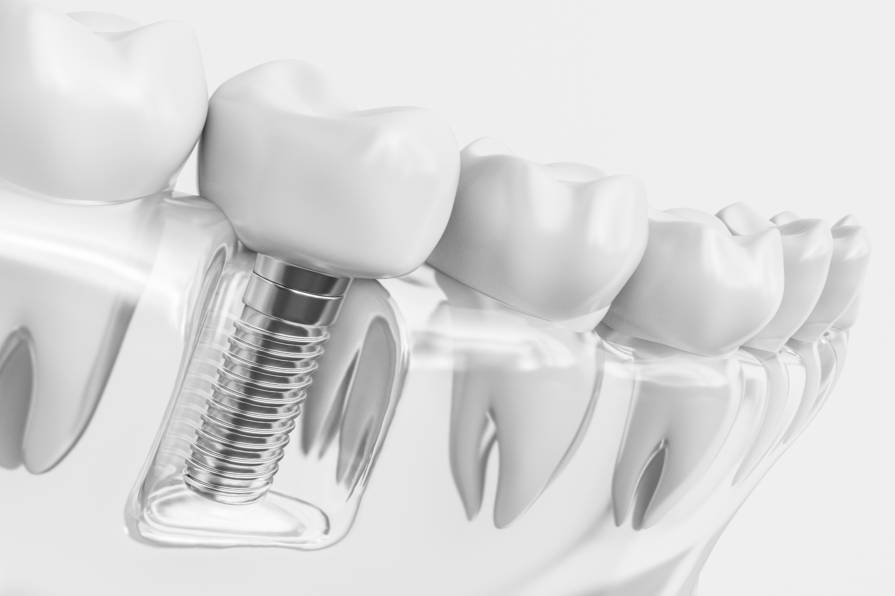

Inplantea

Esperientzia, teknologia eta kalitatea.

- Materi Biokonpatiblea

- 20 urteko baino gehiagoko esperientzia

- BTI inplanteak